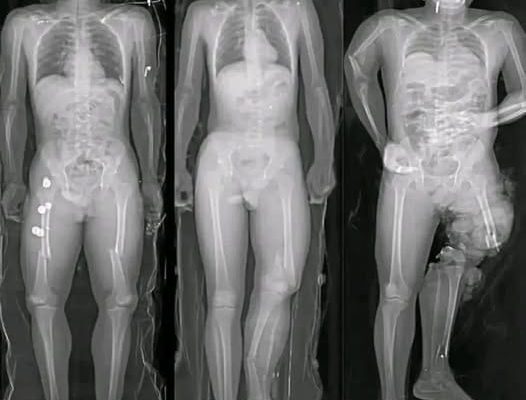

In recent months, a wave of alarming images and short messages has circulated widely across social media platforms, often accompanied by phrases such as “If you got the COVID vaccine, you should know this.” Many of these posts feature dramatic visuals—most notably illustrations of syringes aimed directly at the human heart—designed to provoke fear and urgency. While the images are striking, they rarely provide verified medical context. Instead, they rely on emotional reaction rather than evidence.